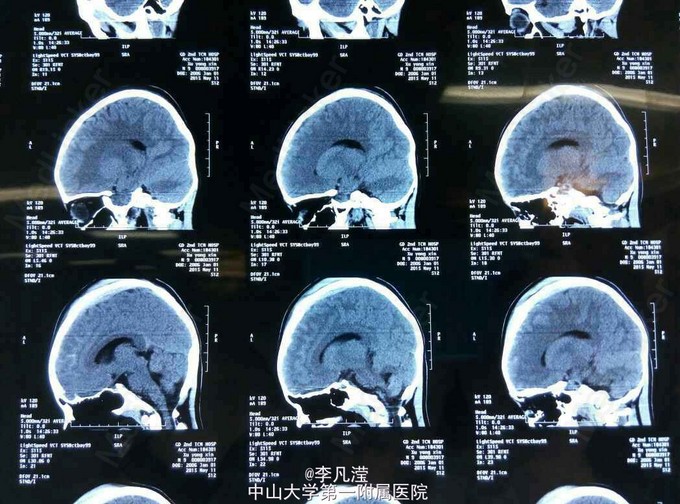

颅骨骨折

头痛、呕吐半小时

颅骨凹陷骨折

右颞部多发颅骨骨折